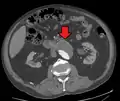

Biomechanical AAA rupture risk prediction An axial contrast-enhanced CT scan demonstrating an abdominal aortic aneurysm of 4.8 by 3.8 cm

An axial contrast-enhanced CT scan demonstrating an abdominal aortic aneurysm of 4.8 by 3.8 cm The faint outline of the calcified wall of an AAA as seen on plain X-ray